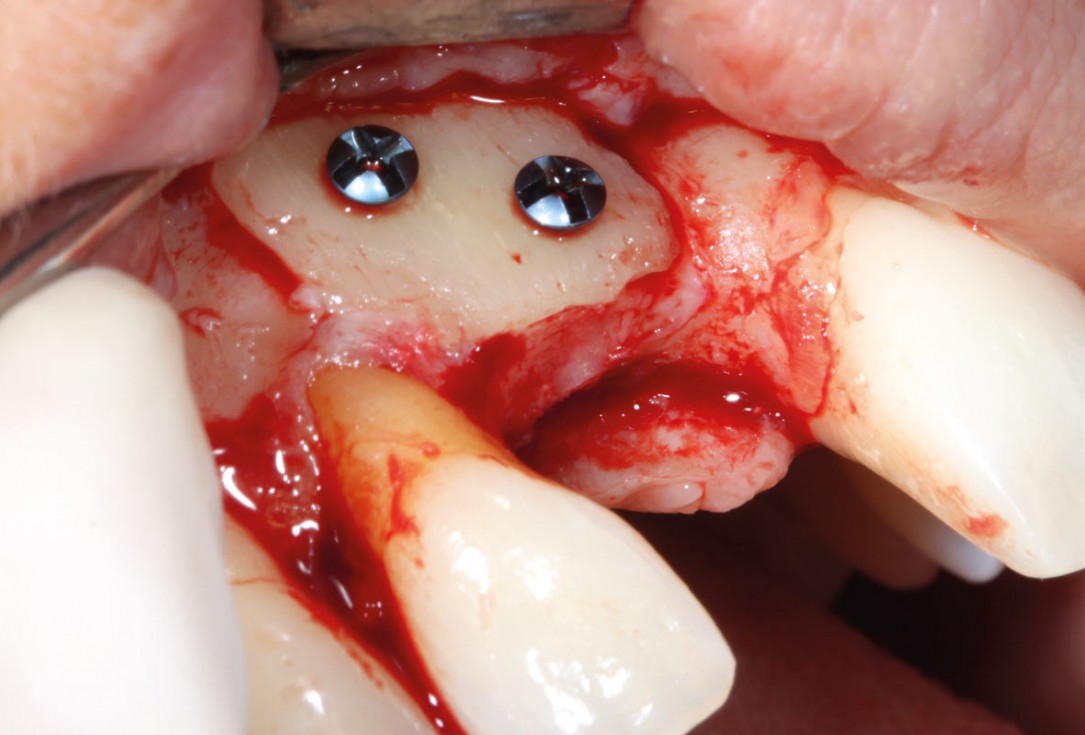

8/11 - Re-entry after 5 monthsmaxgraft® cortico at combined defect palatally and facially - Dr. K. Höckl

9/11 - Solid integration of cortico and implant placementmaxgraft® cortico at combined defect palatally and facially - Dr. K. Höckl